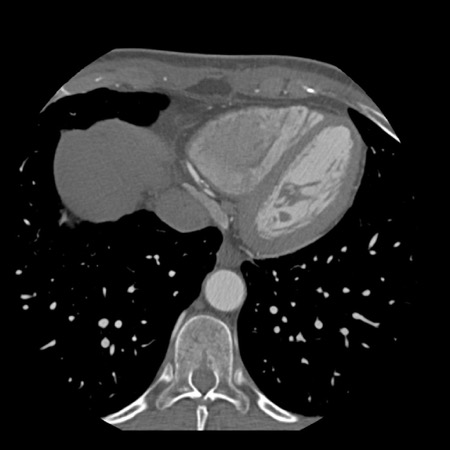

case 1 – CAD-RADS 2/P1

First, scroll through the scan.

Not all images are included. Some images without any abnormalities are skipped

from the series.

How would you describe the findings on the coronary CTA?

The findings are:

- Agatston score of

this patient was 14 (P1). Please, also note the calcification of the aortic valve. - Some partially

calcified and calcified plaques are present in the LAD with mild stenosis

(25-49%). - Calcified-plaque in

the LCX causing minimal stenosis (<25%). - Non-calcified

plaque in the distal RCA causing minimal stenosis (<25%). - This patient classifies

as CAD-RADS 2/P1, which means no further workup is needed.